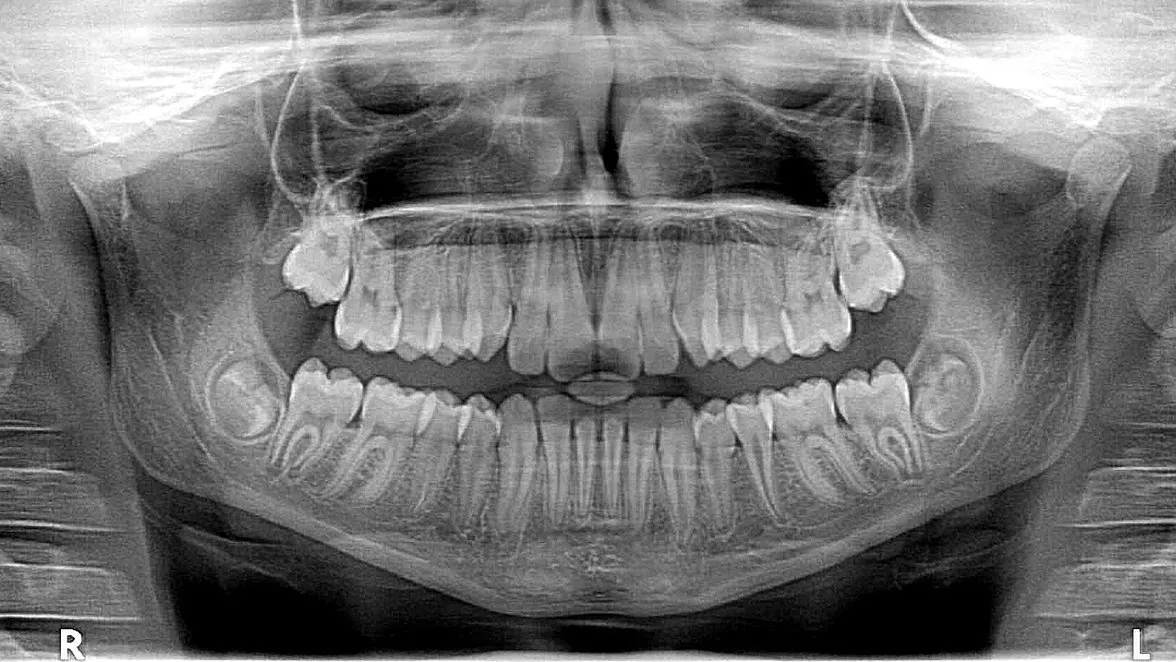

Рейнтген зубов и черепа, фото - Новости Zakon.kz от 26.08.2025 04:59 Фото: pixabay

Признаки нарушений прикуса могут быть неочевидными. Повышенная стираемость эмали, щелчки или хруст в височно-нижнечелюстных суставах, затруднения при жевании, частые боли в области лица и шеи. Нередко пациенты жалуются на ощущение "усталости" челюстей после длительного разговора или приема пищи.

Нарушения прикуса могут также провоцировать бруксизм – непроизвольное скрежетание или сжатие зубов, чаще всего во сне.